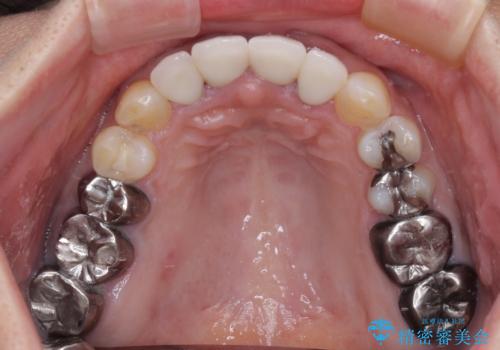

根尖病変が原因で、膿が出てきている歯があったため、仮歯を置き換える際に根管治療を行うこととしました。

仮歯を変えたことで歯肉の腫れは引き、根管治療も功を奏して膿の出口はきれいに消退しました。